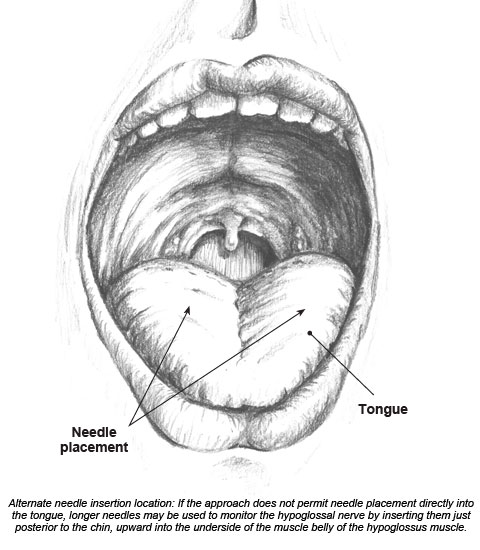

Solved Label the following illustration using the terms | Chegg.com